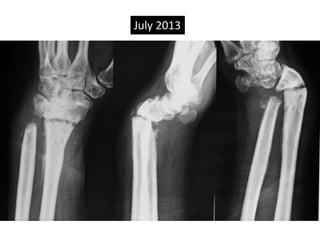

Case two

• 50 years old female

• Low energy injury

• Sustained fracture lower end radius

• Pop cast for six weeks

• Progressively increasing deformity following

removal of plaster.

• X- rays after six months following fracture

showing non-union.

Established non union

Six month old injury